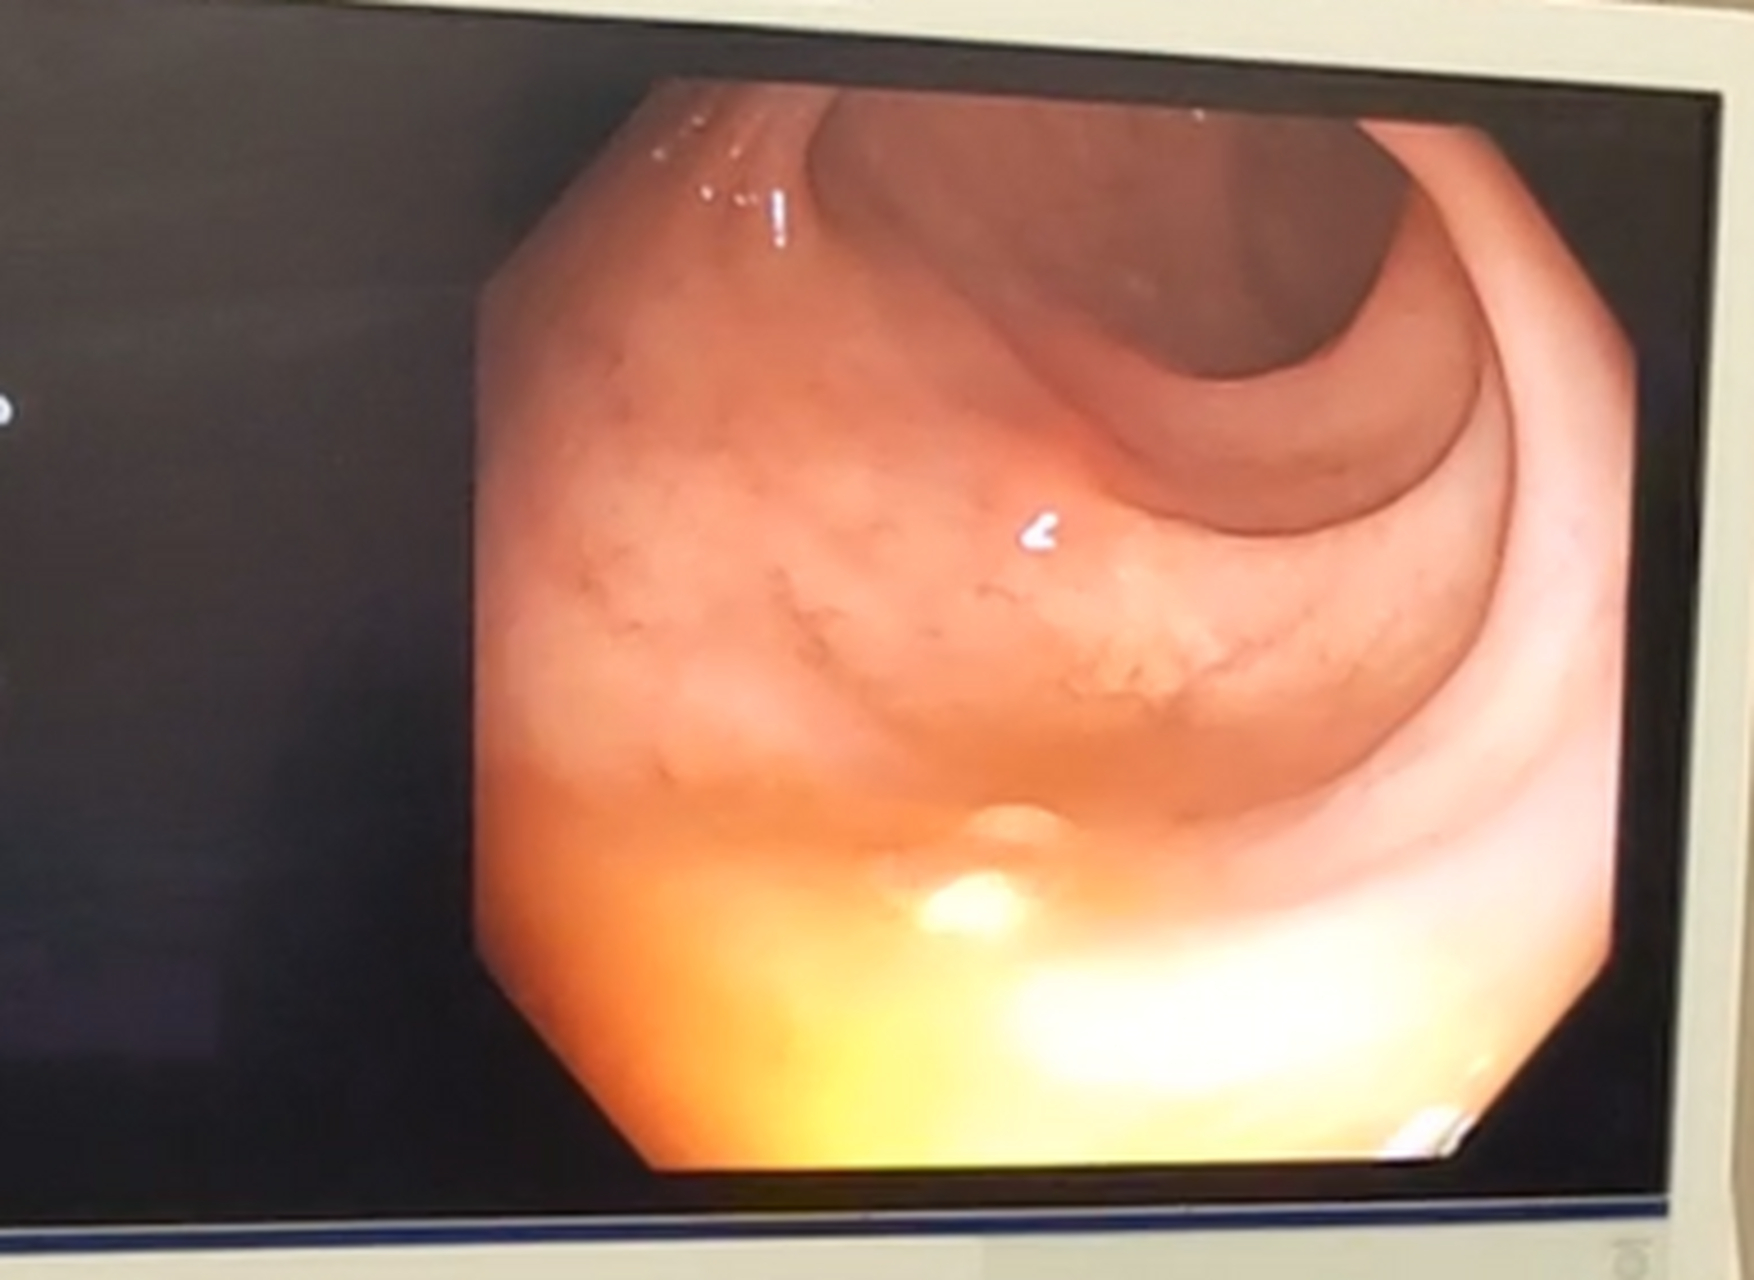

结直肠息肉的严重程度需结合具体情况判断,多数情况下不严重,但需警惕恶变风险结直肠息肉是肠黏膜表面突出的赘生物,多数为良性病变,但其潜在风险与类型大小数量密切相关根据病理特征,息肉可分为腺瘤性息肉恶变风险较高增生性息肉通常无害和炎性息肉由炎症刺激引发等类型其中。

直肠息肉的严重程度需结合息肉大小和病理分型综合评估,并非所有情况均严重从病理性质来看,直肠息肉可分为炎性息肉和腺瘤性息肉两大类炎性息肉通常由慢性炎症刺激引发,属于良性病变,癌变风险极低这类息肉一般不会对健康造成严重威胁,多数情况下无需特殊治疗,但需定期复查以监测变化腺瘤性息肉则。